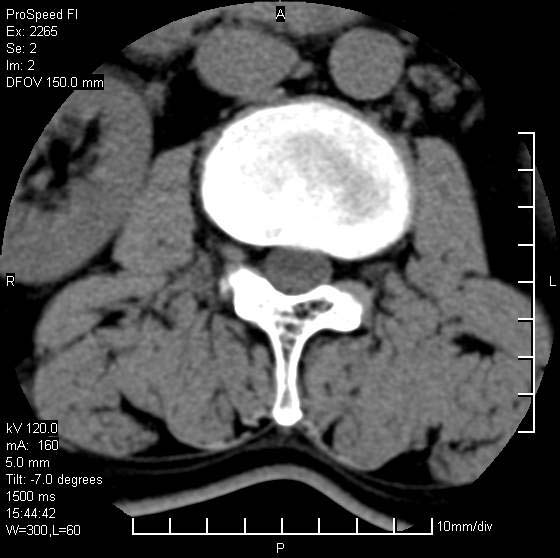

以下是引用qiushi在2007-8-22 17:26:00的发言:[br]没骨窗![br] 1、 l5~s1间盘膨出伴轻度突出(中央型)、变性。[br] 2、l4~5间盘膨出伴突出(右侧远外侧型)。[br] 3、l3~4间盘膨出。[br] 4、腰椎退行性变。[br]

以下是引用随缘的人在2007-8-22 20:56:00的发言:[br]腰椎退行性变:1。l4/5,l5/s1膨出[br] 2。l5/s1间盘退行性变 [br] 3。腰椎骨质增生

以下是引用liaizhi在2007-8-22 22:13:00的发言:[br]1,l4-5锥间盘膨出,2,l5-s1椎间盘膨出并退变(椎间盘呈真空征);3,血管瘤(椎体骨小梁稀疏粗大)?